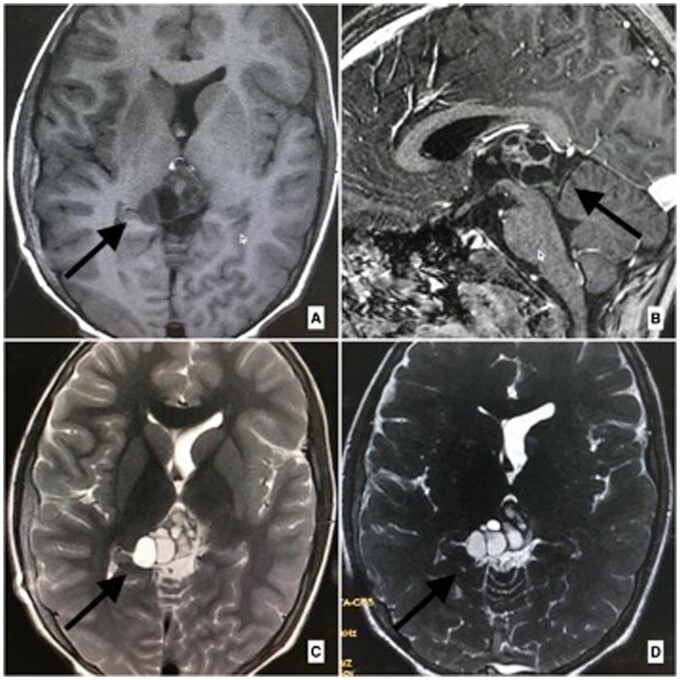

神经囊尾蚴病(NCC)是世界某些地区常见的中枢神经系统寄生虫病。总状型神经囊虫病与常见的实质型神经囊虫病截然不同。它经常浸润基底蝶窦和西尔维窝。影像学检查在诊断中起着至关重要的作用;然而,由于其信号强度与脑脊液相似,而且在大多数病例中没有增强,因此常规 MRI 序列的影像学诊断往往比较困难。在此,我们介绍了五例消旋体 NCC 病例,以强调重 T2 加权序列(快速成像稳态采集)序列在诊断这种疾病中的重要性。

Neurocysticercosis (NCC) is a common parasitic condition of the central nervous system in certain parts of the world. The racemose variety of NCC is distinct from the commonly seen parenchymal form. It frequently infiltrates the basal cisterns and Sylvian fissures. Imaging plays a vital role in the diagnosis; however, as their signal intensity is similar to cerebrospinal fluid and due to the absence of enhancement in most cases, imaging diagnosis is often difficult on the conventional MRI sequences. Here, we present five cases of racemose NCC to emphasize the importance of a heavily T2-weighted sequence (Fast Imaging Employing Steady-state Acquisition) sequence in the diagnosing this entity.